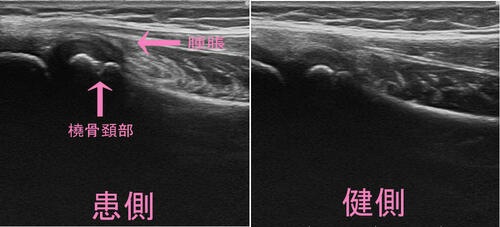

視診、触診で左肘関節に腫脹を触知し、橈骨頭部に圧痛。

エコー検査では炎症反応は診られるが、橈骨表面には異変はなし。

しかし、橈骨頭部の限局性圧痛と関節内に腫脹があることから、

「橈骨頚部骨折」or「橈骨近位端骨端線離開」の疑い。

結果、転移はない「橈骨頚部骨折」

来院時は肘の曲げ伸ばしができ、腫脹がなければ骨折を見落とすところでした。

成長期の橈骨頚部には、骨端線という骨が縦に成長する軟骨があって、